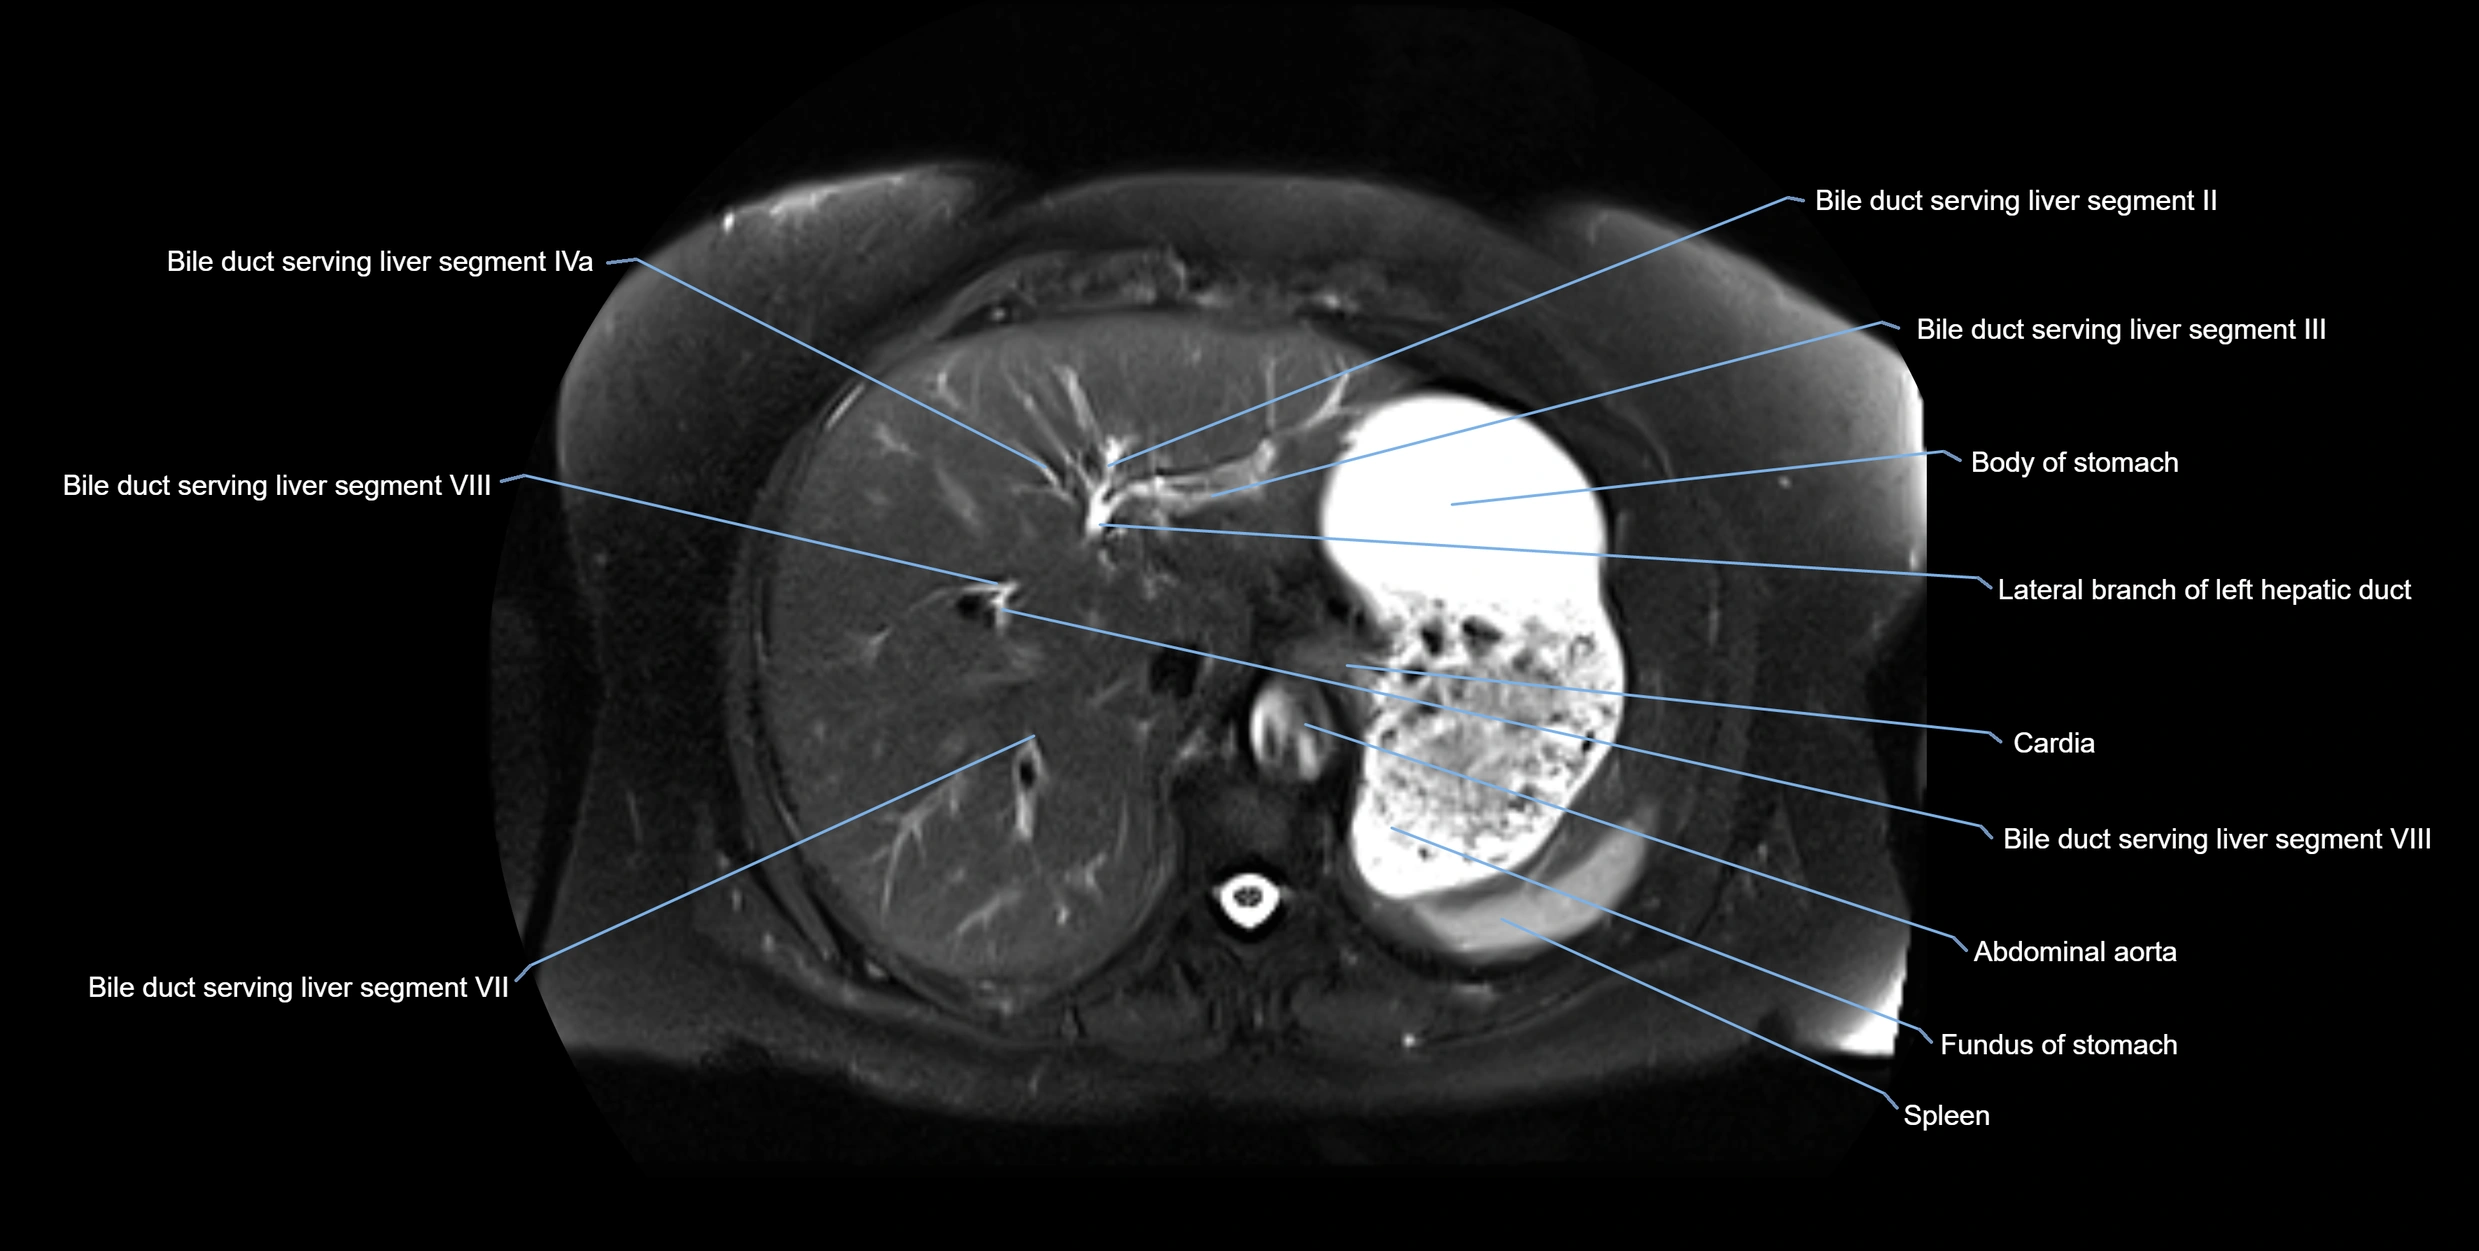

MRI image

image